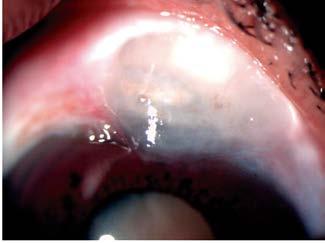

Presentamos el caso de una paciente de 81 años con agudeza visual de ‘cuenta dedos’ en el ojo derecho y antecedente de trabeculectomía, cuya ampolla filtrante superior se encontraba funcional, pero marcadamente adelgazada (Figuras 1 y 2).

A la exploración, destacaba una catarata hipermadura, PIO de 9 mmHg y daño glaucomatoso avanzado (copa/disco 0.9).

La estrategia quirúrgica se definió mediante la microscopia especular y la UBM: un RCE crítico de 997 células/mm² (Figura 3) y un cristalino de gran diámetro anteroposterior con lens vault aumentado (Figura 4).

Figura 1. Catarata hipermadura

Figura 2. Ampolla filtrante avascular y adelgazada

Figura 5. Túnel escleral de la MSICS

Figura 6. Sutura del túnel escleral con un punto de nylon

Figura 7A. Conjuntiva temporal en el postoperatorio

Figura 7B. Ampolla filtrante posterior a MSICS